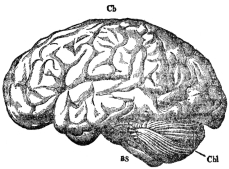

| XI. | The Brain and Complex Nervous Actions | 139 |

Nearly everyone learns in school the main facts about the construction of the body; that there is a bony skeleton which supports the softer parts; that motions are made by muscles; that sense organs inform us as to what is going on in the world around; that the brain is the seat of the mind; that heart, lungs, stomach, kidneys, and other organs contribute in various ways to our well-being. Not so many go into detail as to the make-up of these organs, or into the way in which they do their work. This is not a simple matter, for several reasons. The first is that the construction units are so tiny that they cannot be seen by the unaided eye, but must be studied under the high magnification of a first-class microscope. It is much harder to make out the manner of the working of tiny pieces of machinery than of those that are of convenient size. When the parts are as small as those that make up our bodies, the task of finding out how they operate is so difficult that even now, after years of study, there are many details about which we know very little.

A GOOD deal has been said thus far about living cells without anything at all having been said to tell what they look like, or how they are made up, beyond the statement that they consist of living protoplasm, which is of a jellylike consistency. To look at living cells through a microscope would almost surely be a disappointment at first, for protoplasm is so transparent that not much of its form can be seen on direct inspection. Fortunately for our knowledge of how cells are made up, protoplasm that has been properly killed and preserved takes stain very well, and different chemical substances in the protoplasm stain differently. Thus features that could not be made out at all in the living cells become clearly visible after killing and staining. The first thing that attracts the attention when cells thus prepared are studied is that every cell has somewhere within it, and usually near its middle, a spot which is more deeply stained than any other part of the cell. This indicates the presence of a substance or substances that take stain more readily than the mass of the protoplasm. This peculiarity led to the naming of the deeply staining portion of the protoplasm chromatin, referring to the ease of staining. The part of the cell which contains chromatin is called the nucleus. In many kinds of cells the nucleus can be made out by an expert observer without resorting to stains, although the details of structure cannot be seen in that way.

We now know that the nucleus, or rather the chromatin that it contains, plays a remarkable and interesting rôle in the life of the cell. To this we shall return presently. The remainder of the protoplasm, outside of the nucleus, shows the greatest possible variety of form, according to the kind of cell at which we happen to be looking. In some of the simpler types this part of the protoplasm seems to be merely a nearly uniform mass, perhaps with tiny particles scattered through it. In other types the protoplasm is drawn out into long slender threads, and these threads may have many branches; or the protoplasm may be distorted into a thin shell inclosing a mass of fat; or it may be subdivided into dense and thin portions with sharp lines of division between them. These various forms are related to the special functions which the cells have, and we shall learn more about them as we take up the different functions in order. On the whole, study of cell structure shows clearly that the protoplasm outside the nucleus carries on the greater part of the metabolism or power development, and is correspondingly important as the seat of the special functions shown by the cell. If it is a muscle cell, this is the part that does the moving; if a gland cell, this is the part that secretes. Nevertheless, the nucleus is a vital part of the cell. It has been definitely proven that a cell from which the nucleus is lost cannot survive more than a brief time. To gain some idea of the actual part played by the nucleus, we shall have to return to it in some detail.